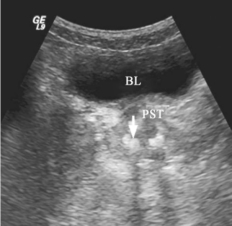

前列腺内外腺交界处及沿射精管和尿道周围见多个点状或团块状强回声,可伴声影(图31-2)。

图31-2 前列腺结石声像图